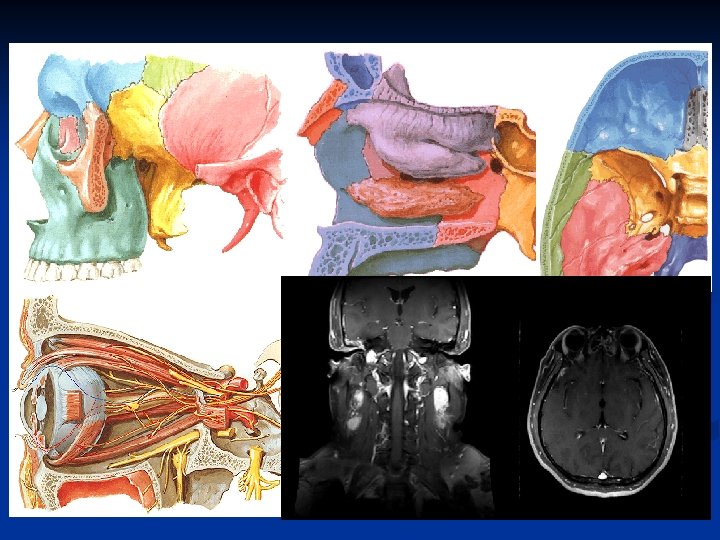

Orbit n Keywords: -- Extraconal & Intraconal -- Lacrimal glands -- Muscles -- Superior & inferior orbital fissures -- Optic canal

Superior & inferior orbital fissures